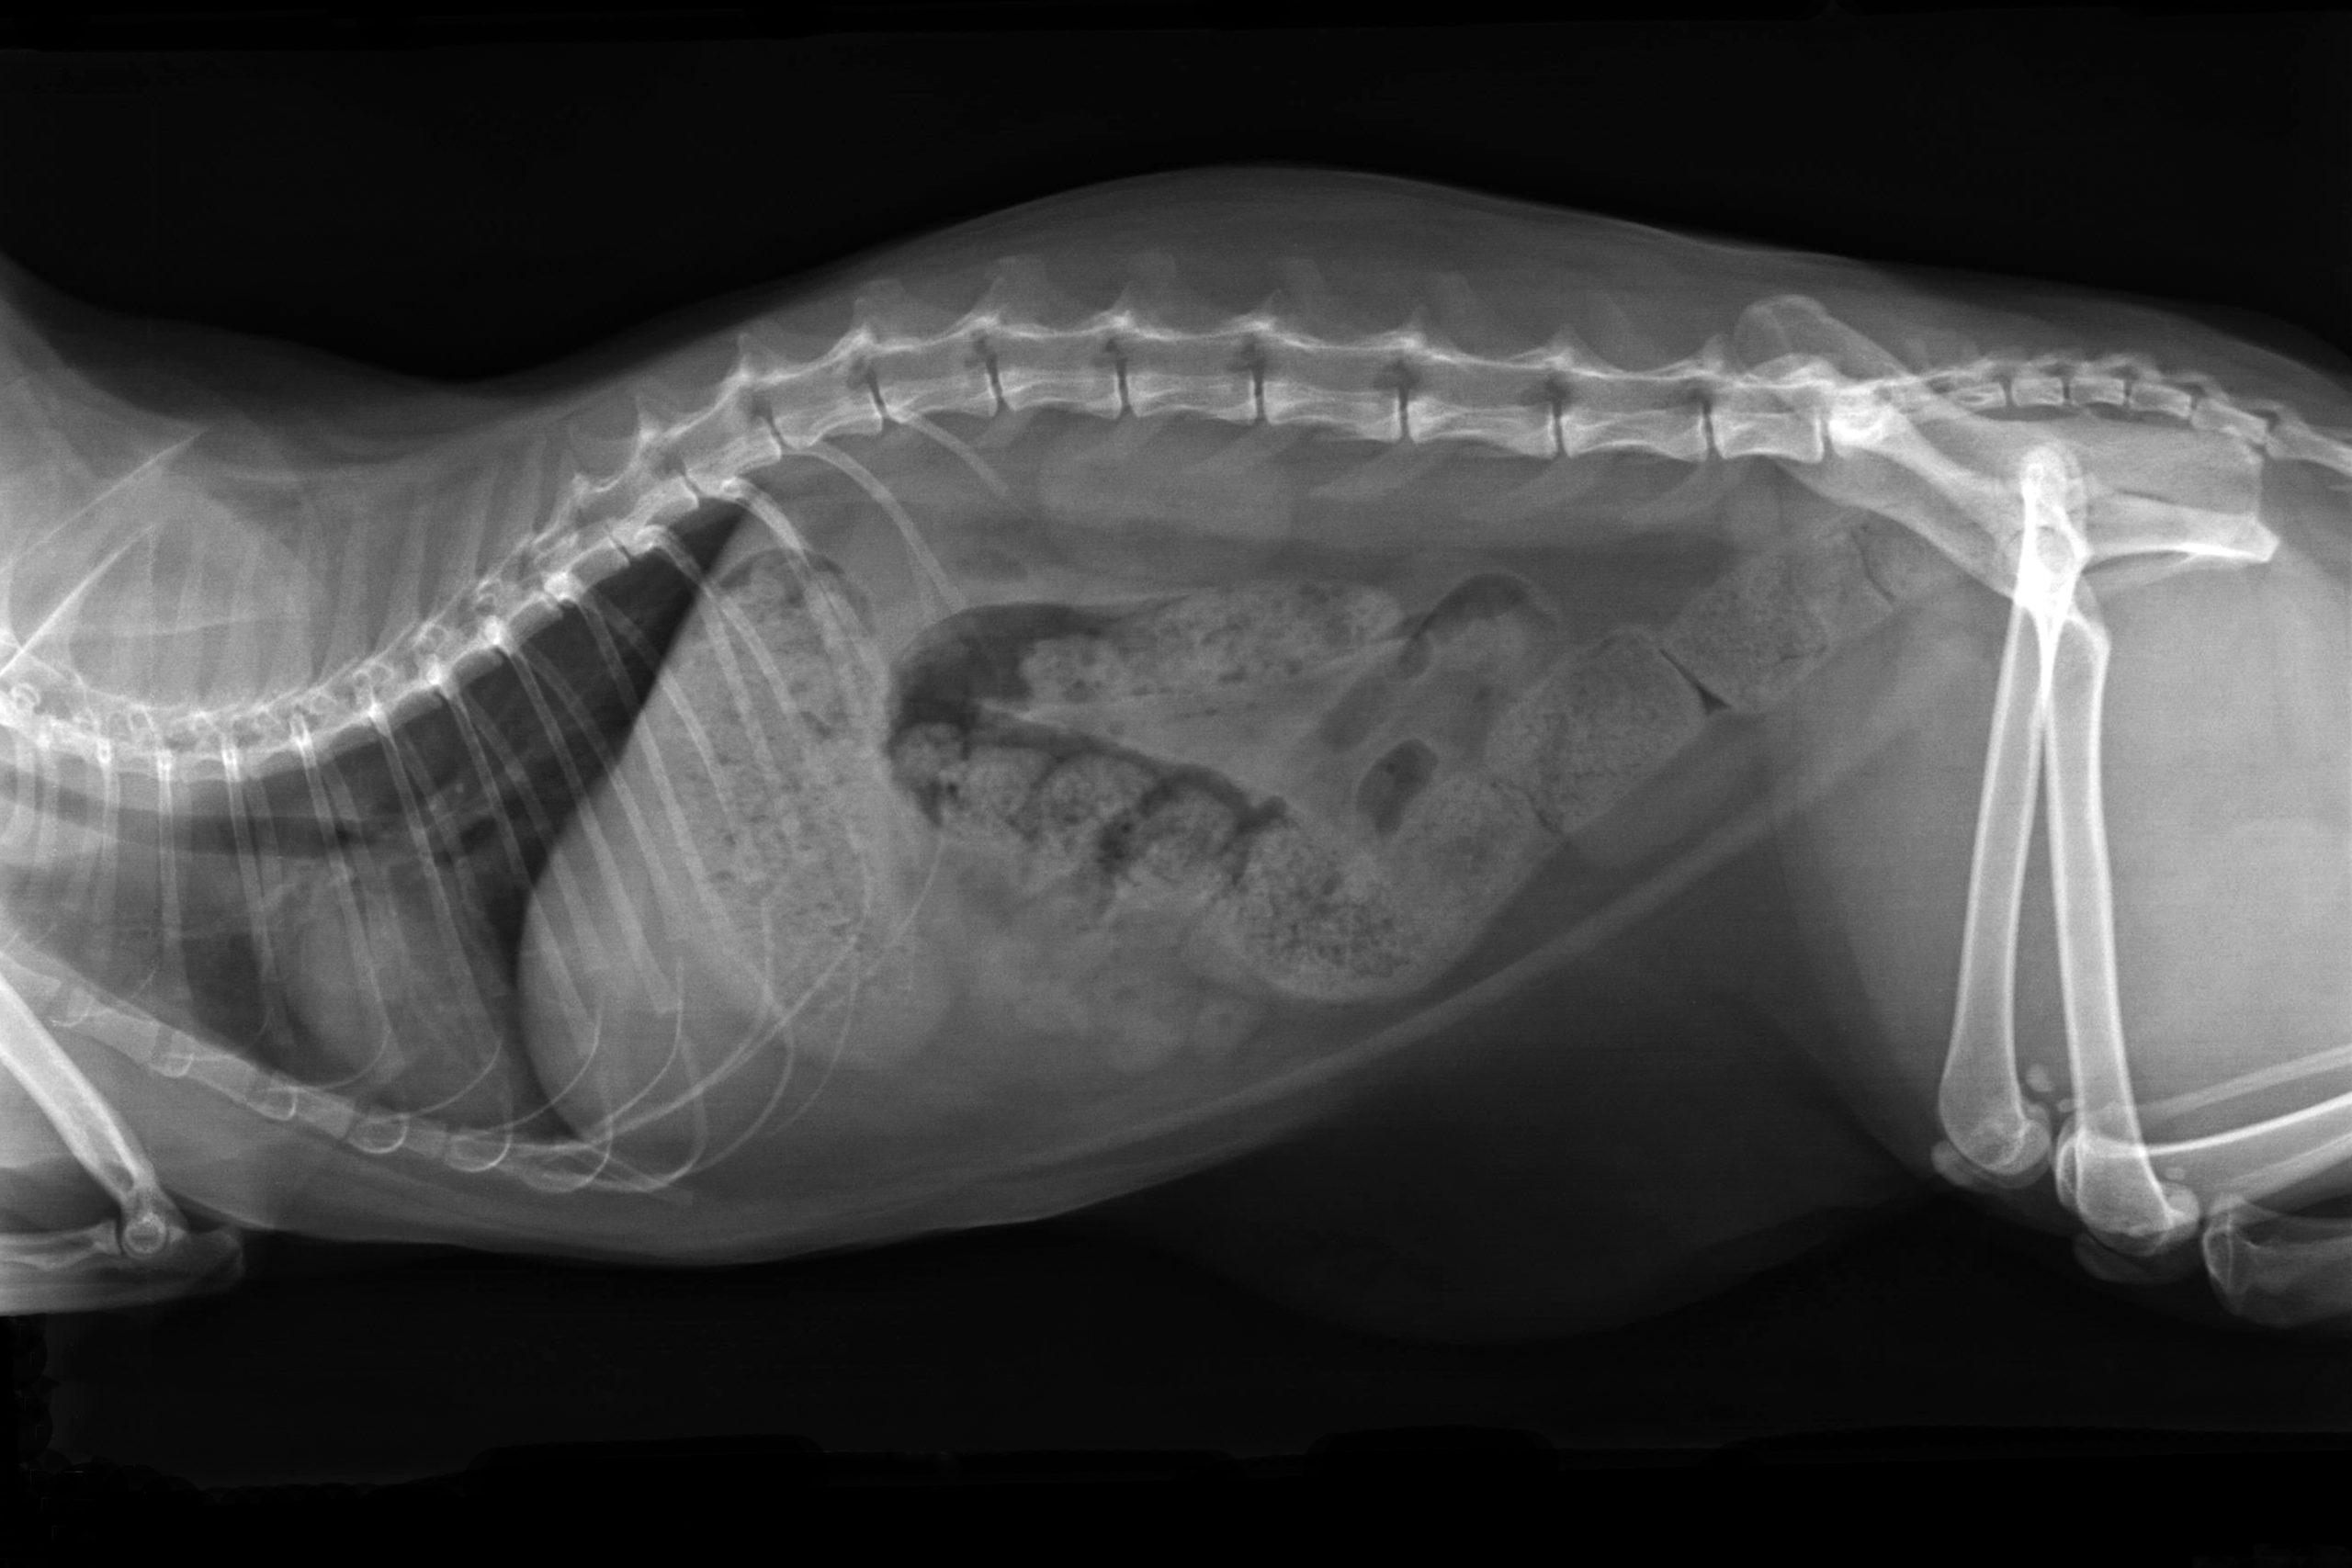

- Problemi digestivi*

*= Radiografia di un gatto in sovrappeso con blocco intestinale completo. Vista laterale.